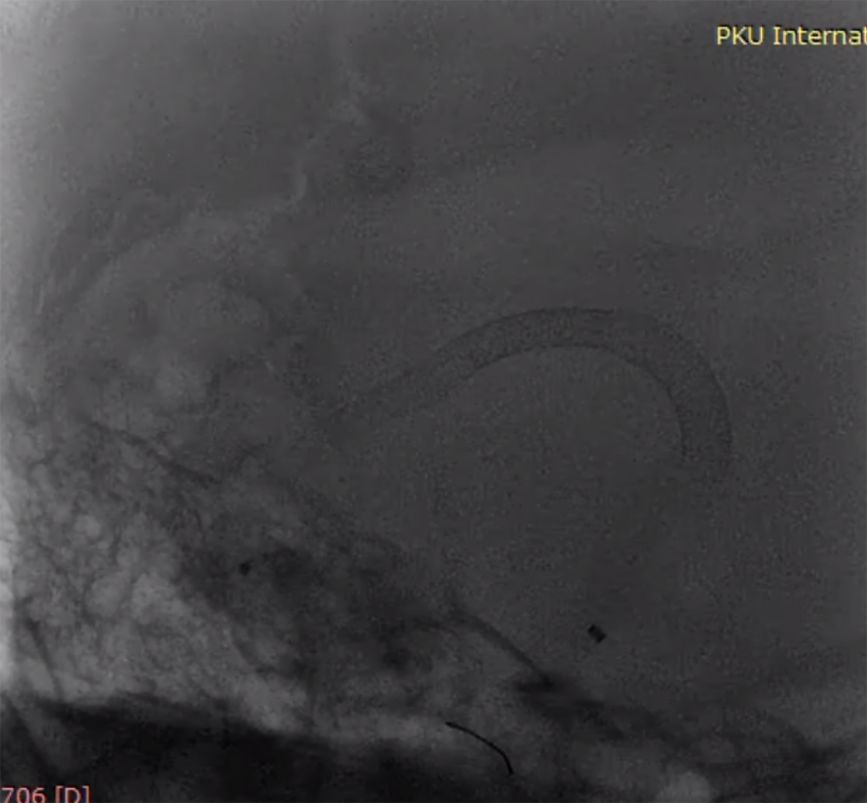

(2)左颈动脉造影见大脑前动脉抬高,右侧颈内动脉球囊闭塞试验见前交通动脉开放,M1段显影不良,考虑后交通供血较强(图2)。

图2

(3)后循环造影及右侧颈内动脉球囊闭塞试验,提示后交通供血较明显,可见动脉瘤显影,无法闭塞颈动脉,选择行动脉瘤栓塞术(图3)。

图3